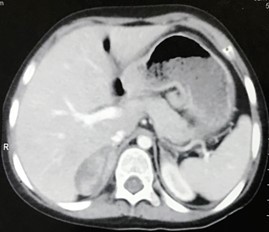

Figure 3: CT Abdomen showing right adrenal mass